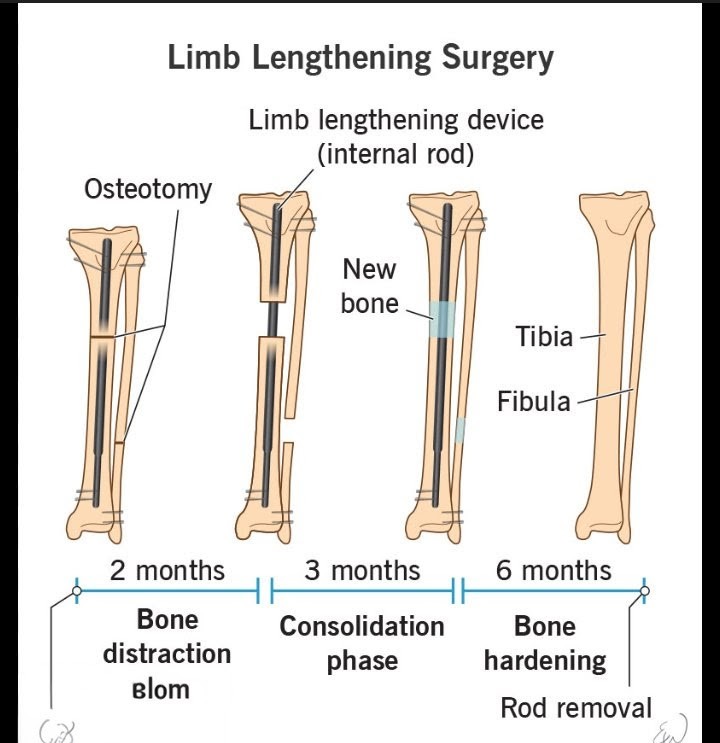

11. Limb lengthening

11. Limb lengthening